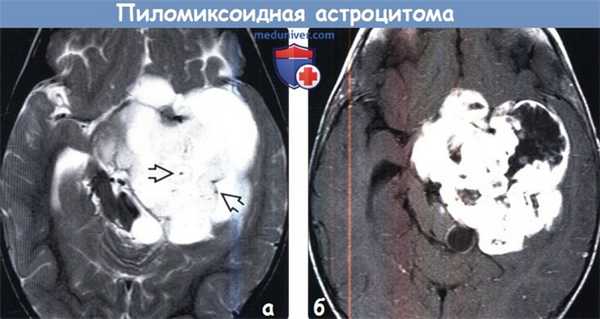

(а) MPT, Т2-ВИ, аксиальный срез: у 20-месячного ребенка в супраселлярной области и медиальной части височной доли определяется крупное, массивное объемное образование. Очаги с укорочением Т2 в структуре образования могут отражать кровоизлияния (Т2* изображения получены не были).

(б) МРТ, постконтрастное Т1-ВИ, аксиальный срез: у того же пациента определяется смешанный (солидный и краевой) характер контрастного усиления. При биопсии были обнаружены удлиненные «пилоидные» клетки в матриксе, богатом муцином, что характерно для пиломиксоидной астроцитомы (ПмA).